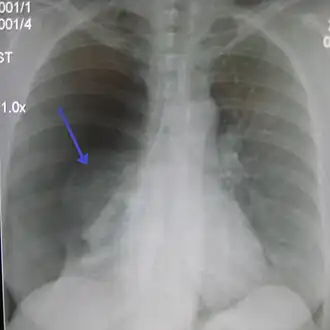

![]() Правосторонний спонтанный пневмоторакс (слева на изображении). Стрелкой указан край спавшегося лёгкого. | |

Рентгенография органов грудной клетки

- Для подтверждения диагноза необходимо проведение рентгенографии грудной клетки (оптимальная проекция — переднезадняя, при вертикальном положении больного).

- Рентгенографическим признаком пневмоторакса является визуализация тонкой линии висцеральной плевры (менее 1 мм), отделённой от грудной клетки.

- Частой находкой при пневмотораксе является смещение тени средостения в противоположную сторону. Так как средостение не является фиксированной структурой, то даже небольшой пневмоторакс может вести к смещению сердца, трахеи и других элементов средостения, поэтому контралатеральный сдвиг средостения не является признаком напряжённого пневмоторакса.